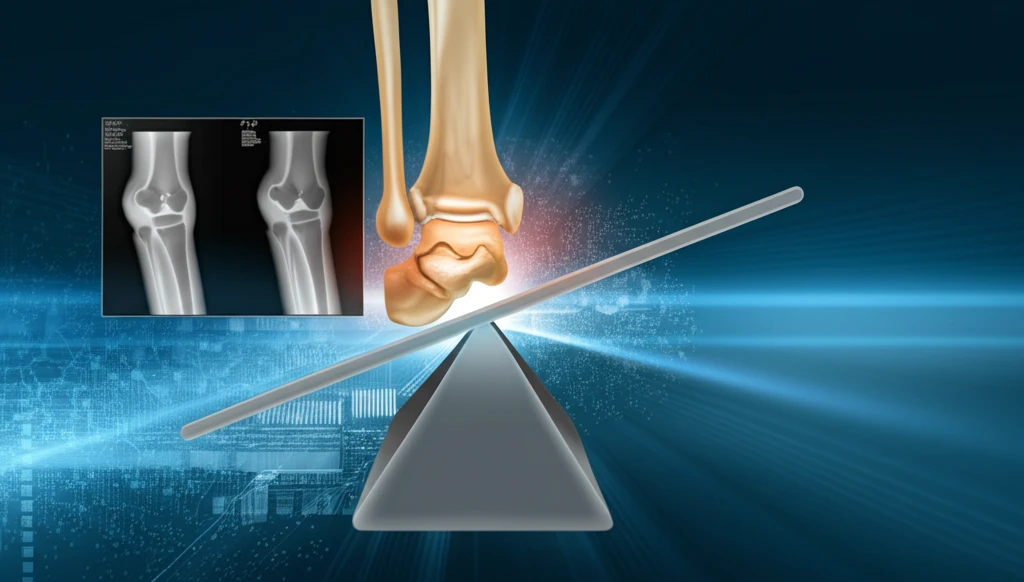

Ankle osteoarthritis, a debilitating condition causing pain and limited mobility, often results from asymmetrical joint loading. Supramalleolar osteotomy (SMO) has emerged as a joint-preserving surgical option aimed at correcting lower limb deformities and redistributing weight evenly across the ankle joint. This procedure is particularly relevant for younger, active patients who wish to avoid or delay total ankle replacement.

The primary goal of SMO is to realign the ankle joint by making a precise cut in the tibia (the larger bone in the lower leg) just above the ankle. By doing so, surgeons can correct deformities like varus (bow-legged) or valgus (knock-kneed) alignment, which contribute to uneven wear and tear within the joint. The correction aims to restore a more normal mechanical axis, reducing pain and improving function.

While SMO has shown promise, one critical question remains: Can it effectively correct tibiotalar tilt, an angular deformity between the tibia and talus (the bone that forms the lower part of the ankle joint)? A recent study by Barg and Saltzman (2017) delves into this issue, evaluating the short-term clinical and radiographic outcomes of patients undergoing SMO performed by a single surgeon. Their findings shed light on the potential—and limitations—of this procedure in addressing tibiotalar tilt.